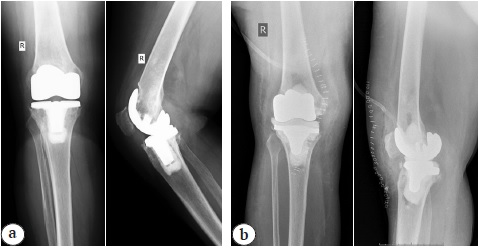

In the group 1 intraoperatively fabricated cement liner was installed between the officinal femoral and tibial implants (Fig. 3).

Fig. 3. X-rays of a 52-year-old patient (2014): a — before surgery; b — after the articular spacer implantation